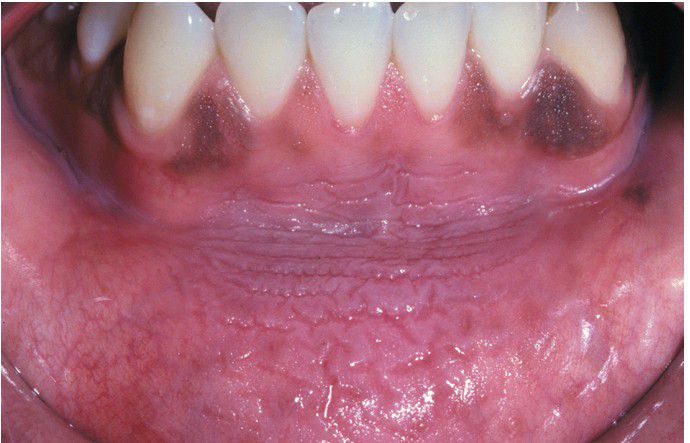

Tobacco Pouch Keratosis, Mild

. A soft, fissured, gray-white lesion of the lower labial mucosa located in the area of chronic snuff placement. The gingival melanosis is racial pigmentation and not associated with the keratosis.